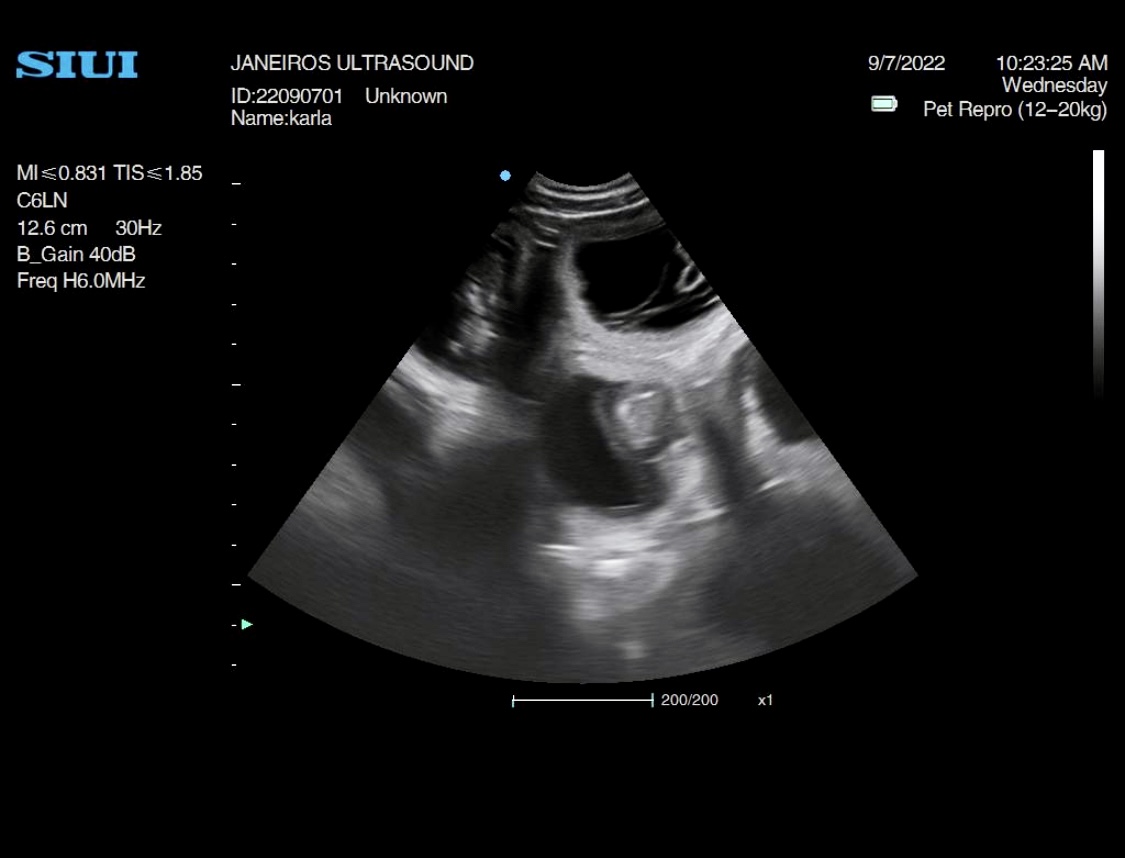

This stunning girl I scanned this morning. She was quite hyper so it was a task getting her to keep still. she has quite a few babies in there I counted at least 10!!

UPDATE….The puppies have arrived and all 10 are doing well 😊 pictures below.